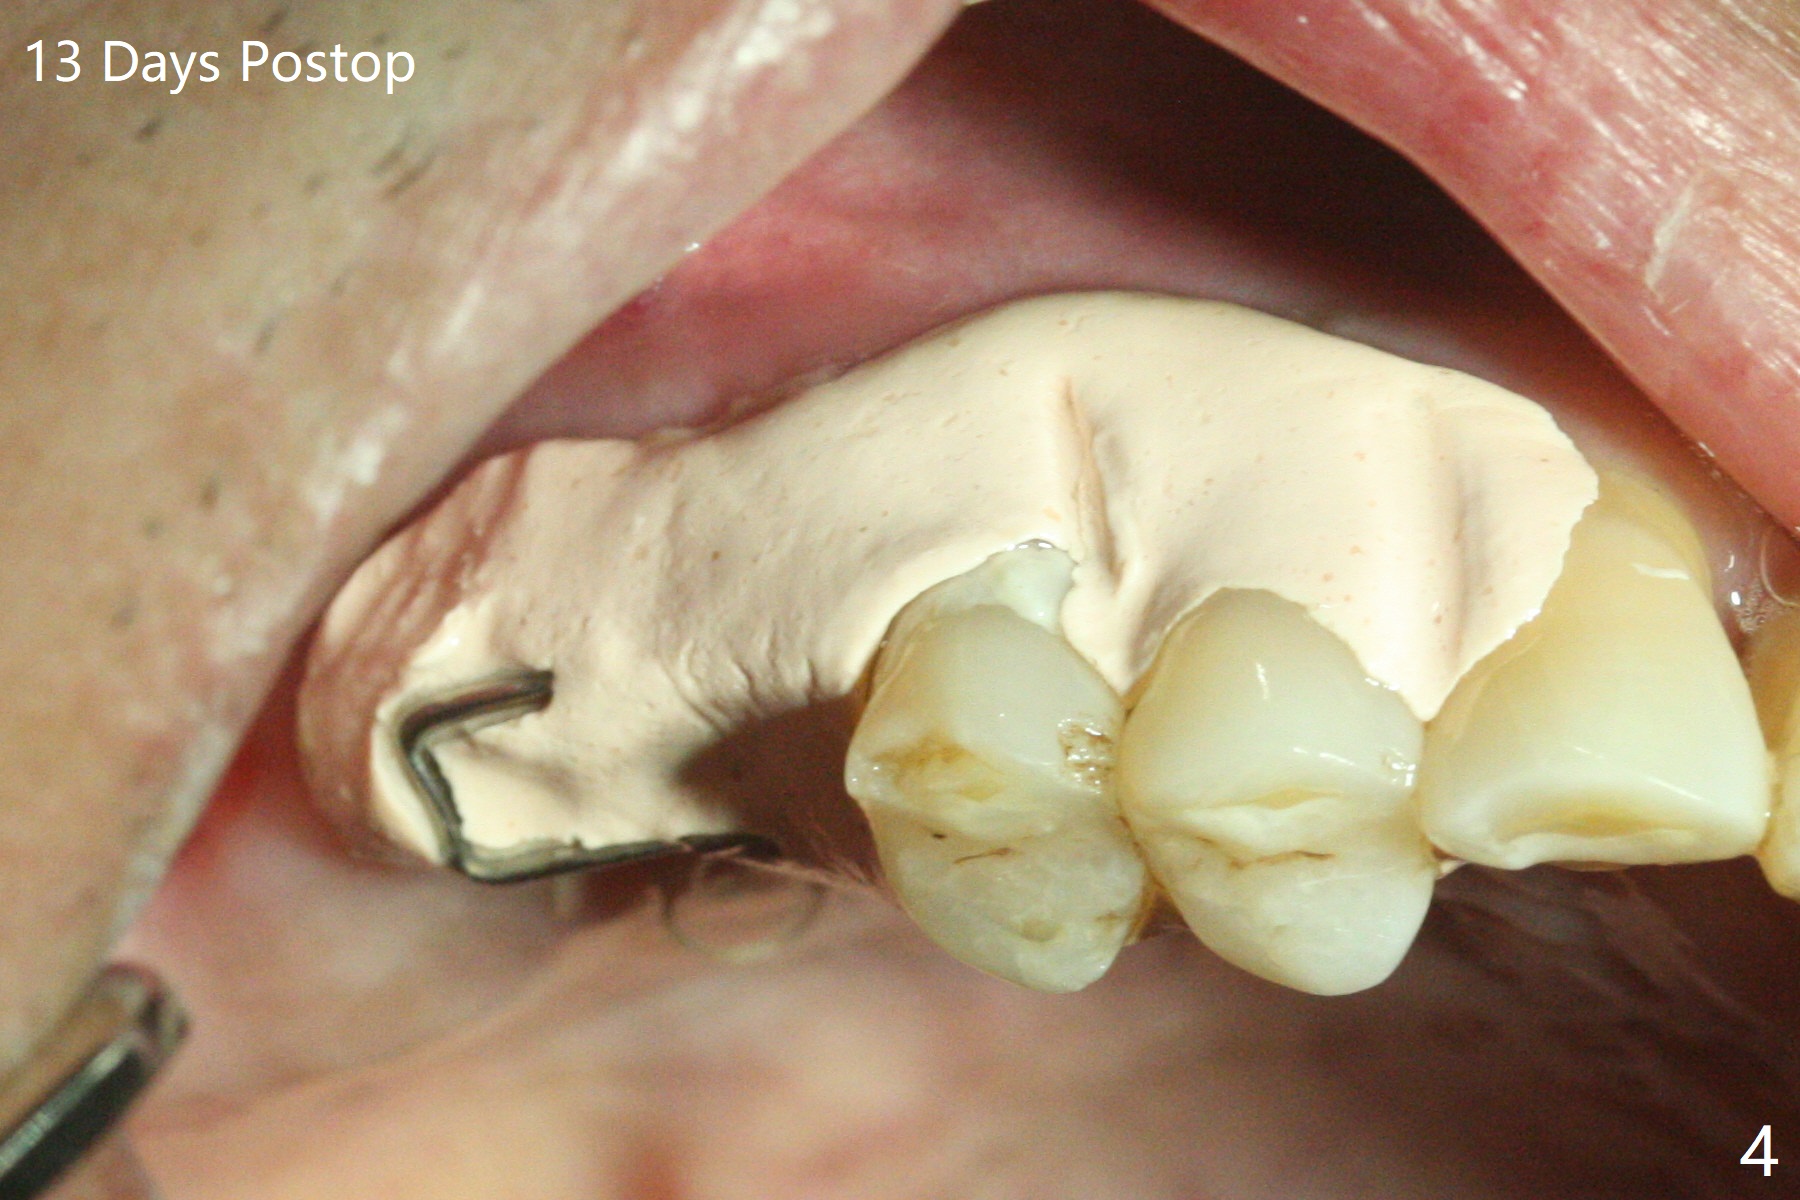

69岁男2.5年前CT显示右上7根尖骨质很薄(图一:*),大约一年后拔除,没植骨。上周拔除8时,发现6腭侧牙周袋出脓(图二:<)。拔除后者清创后,往远中牙龈下分离7位点,然后6,7植骨(图三:*),7骨质高度增加一倍(植骨后近7毫米)。覆盖两片PRF膜,近中放置小块胶原塞(牙槽嵴高),4-0 PGA缝合,置放间隙保持器(放置攀(loop),增加固位)和牙周敷料。术后13天敷料保持原位,卫生也好(图四),病人明天到外地几个月,交代他两周后撤除敷料。没有不便,不必去掉保持器。